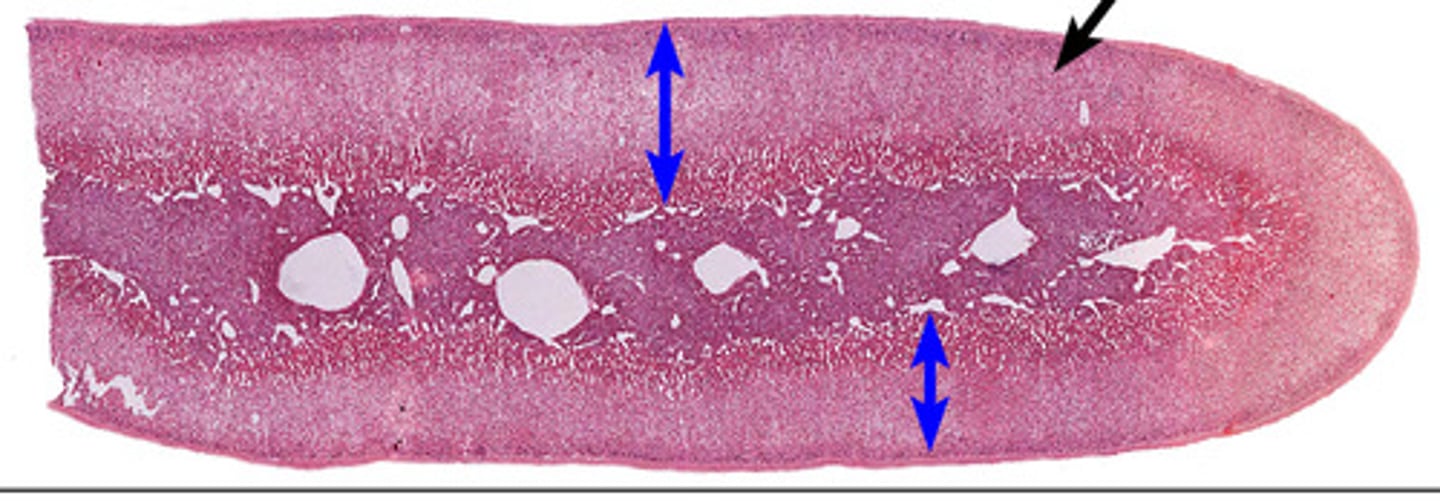

Adrenal gland

Adrenal cortex

Zona glomerulosa

Zona fasciculata

Zona reticularis

Adrenal medulla